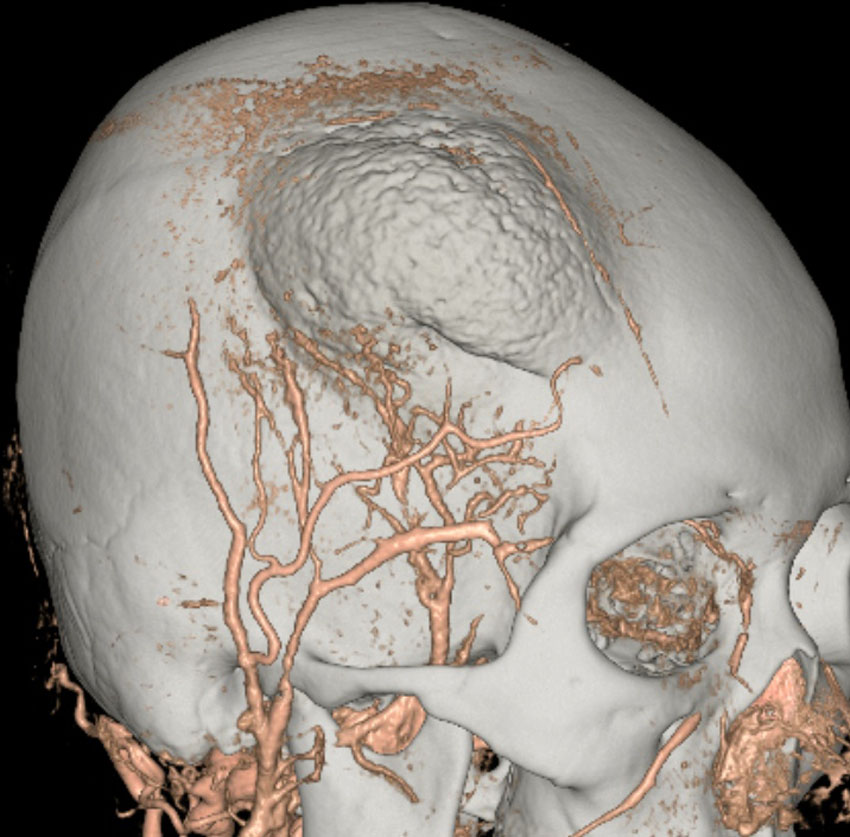

骨内増殖をする髄膜腫です。頭蓋骨腫瘍と間違えるようなものです。触った感じは骨腫ですが,CTでは,表面が毛羽立っていて,頭蓋冠に浸潤していることが特徴です。浅側頭動脈からの豊富な血流があります。

わずかですが頭蓋内にも腫瘍があり,硬膜が肥厚してガドリニウム増強されます。

頭蓋骨をかなり広範におかすので骨は捨てません。開頭して取り外した骨の厚くなっている部分と髄膜腫で軟らかくなっている部分を削除して,それから骨片をオートクレーブで短時間熱処理して,元あった所にもどします。下の画像は手術後1年半が経過したものですが,髄膜腫の再発はなく,熱処理骨弁は吸収されないで生着しています。